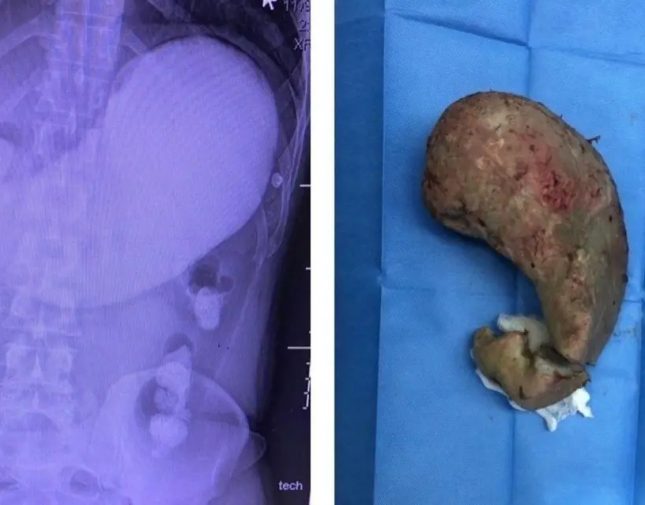

أقدم عامل باكستاني مقيم بمدينة جدة على الانتحار بأغرب طريقة، عبر بلع خليط إسمنتي تجمد داخل أحشائه، ما أدى إلى انسداد تام في المعدة.

وحسب "العربية.نت" قالت إدارة الصحة في جدة، أنه تم نقل المريض إلى مستشفى الملك عبد العزيز بجدة على إثر الآلام التي انتابته إلى الطوارئ حيث تم إجراء كافة التحاليل والأشعة اللازمة له.

وأضافت: أنه "على الفوز تم إدخاله إلى غرفة العمليات بالمستشفى حيث تمكن طاقم طبي وفني من استخراج الجسم الإسمنتي من معدته، وإعادة إصلاح الأضرار التي طالت نسيج المعدة في عملية استغرقت ما يقارب الثلاث ساعات".